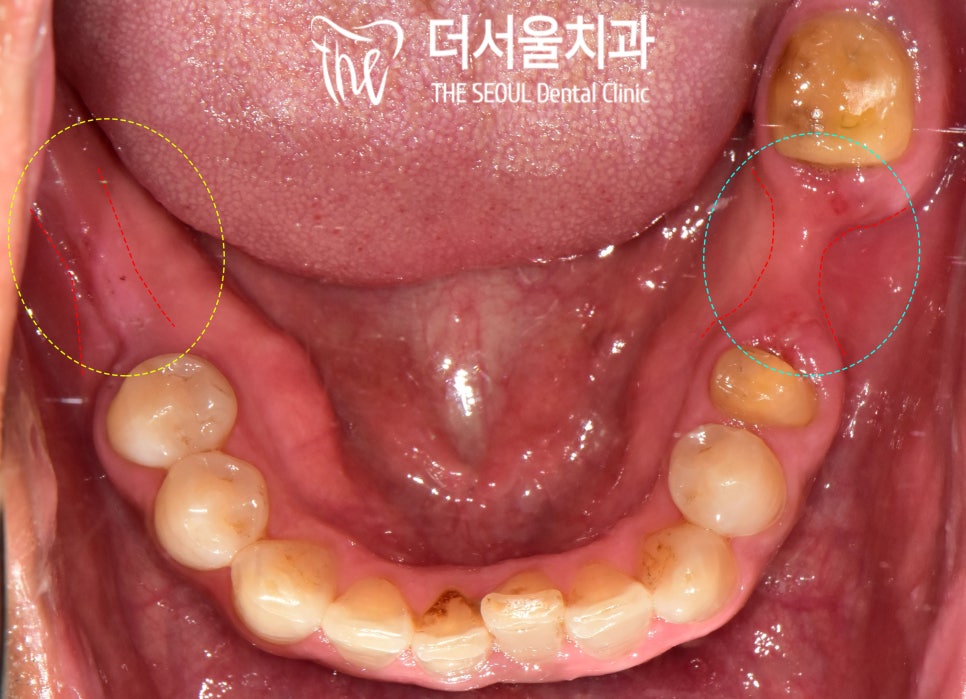

【 구강 검진 및 진단 】

양쪽 아래 어금니가 없어서

식사가 힘드시고,

왼쪽 아래 브릿지가 떨어졌다며

이 부분을 해결하기 위해

성남 치과의원 에 오신 환자입니다.

예전에는 병원이 그렇게 무섭지 않았는데

어느 순간 심한 공포감이 생겨

이가 빠진 채로 오랜 기간

불편하게 생활하셨다 합니다.

파노라마 엑스레이를 찍어 살펴보니

왼쪽 아래 (30번대)와

오른쪽 아래(40번대)의

어금니 결손이 확인되었으며

장시간 방치되어 있던 탓에

치조골도 많이 퇴축되어 있었습니다.